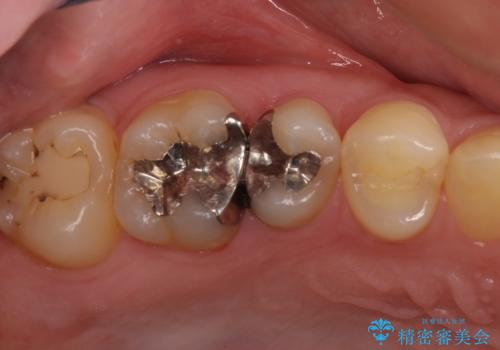

セラミックインレー 痛む歯の治療